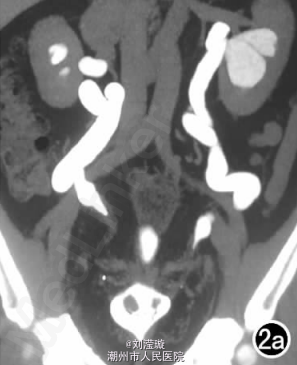

腹部B超示双肾增大,双肾慢性肾病声像;双肾中度积液伴双输尿管上段扩张。 IVPshi双侧输尿管中或下段梗阻。 膀胱造影:经尿道置管后,注射对比剂充盈膀胱,膀胱下半部先充盈,继续灌注对比剂后见膀胱完全显影,膀胱形态异常,呈“倒葫芦状”(图1)。 CT增强扫描行延迟期 MPR重组,见双侧肾盂、肾盏扩张积液;双侧输尿管纡曲、扩张,下端呈鸟嘴样变窄;膀胱变形、体积减小(图2); MRI平扫示双侧肾盂、肾盏扩张积液,双侧输尿管扩张并下端鸟嘴样变窄,盆腔内多量脂肪沉积,分布于膀胱、直肠周围,T1WI、T2WI呈明显高信号,T2WI抑脂像呈稍高信号,膀胱受压变形、体积减小(图3a~c); MRU示双侧肾盂肾盏扩张、积液,双侧输尿管显著纡曲、扩张,下端鸟嘴样变窄,管壁光整,膀胱变形、体积较小、位置抬高(图3d)。